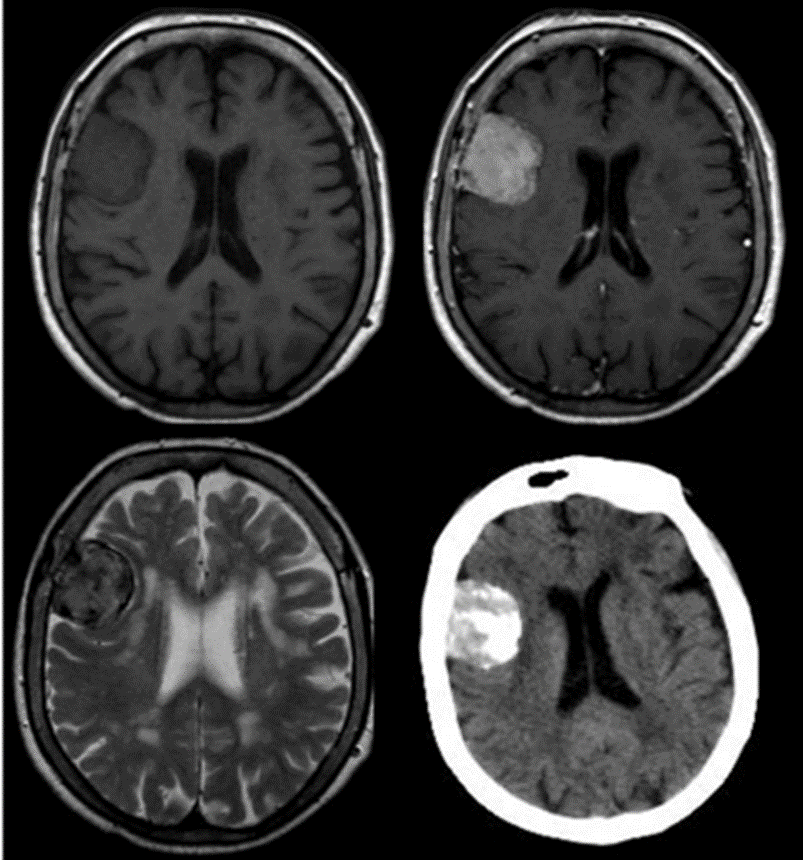

En cuanto a las características de estos tumores en RMI es ampliamente aceptado que las calcificaciones y un comportamiento iso-hipointenso en secuencia T2 está asociado a nulo o muy lento crecimiento (fig 1). El edema peritumoral ponderado en secuencia T2 es un factor para indicación quirúrgica de inicio o un seguimiento estrecho ya que implica mayor tasa de crecimiento 2,3. Para el seguimiento por imágenes es importante un protocolo de control basado en volumetría tumoral y un registro de las curvas de crecimiento. Las medidas lineales, sobre todo en fosa posterior, y la apreciación subjetiva del especialista en diagnóstico por imágenes puede llevar a confusión 4,5,9.

Figura 1: RMN y TAC de paciente de 82 años con imágenes compatible con MI, Isointenso en T1 y realce con gadolinio e Hipointenso en T2, tumor calcificado confirmado por la TAC. La paciente fue seguida durante 8 años sin cambios clínicos ni imagenológicos.